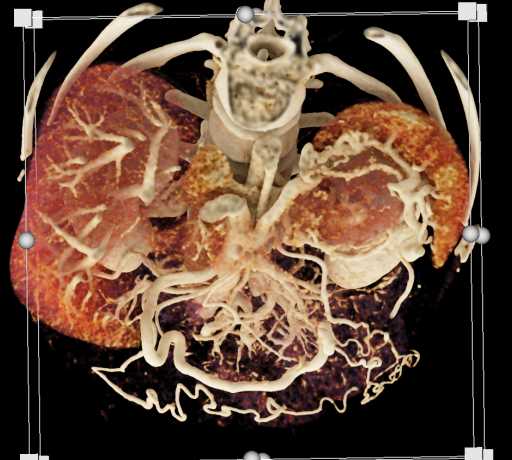

Neuroendocrine Tumor Pancreas